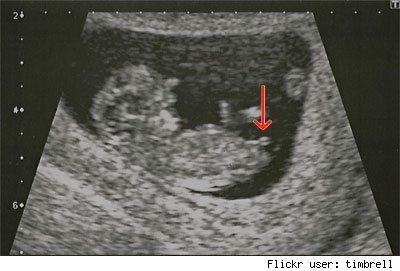

Ciao ragazze! avete mai sentito parlare di questa nuova teoria? Ho trovato su internet, quanto segue : ll riconoscimento del sesso del feto attraverso l’ecografia è possibile dalla 16° settimana mediante visualizzazione diretta dei genitali esterni....

Allora, venerdì sono stata dal medico di base per farmi prescrivere le analisi per il primo trimestre! Parlando del più e del meno, mi disse che molte persone di affidano al "metodo del calendario lunare", chi per il taglio di capelli, chi per il...